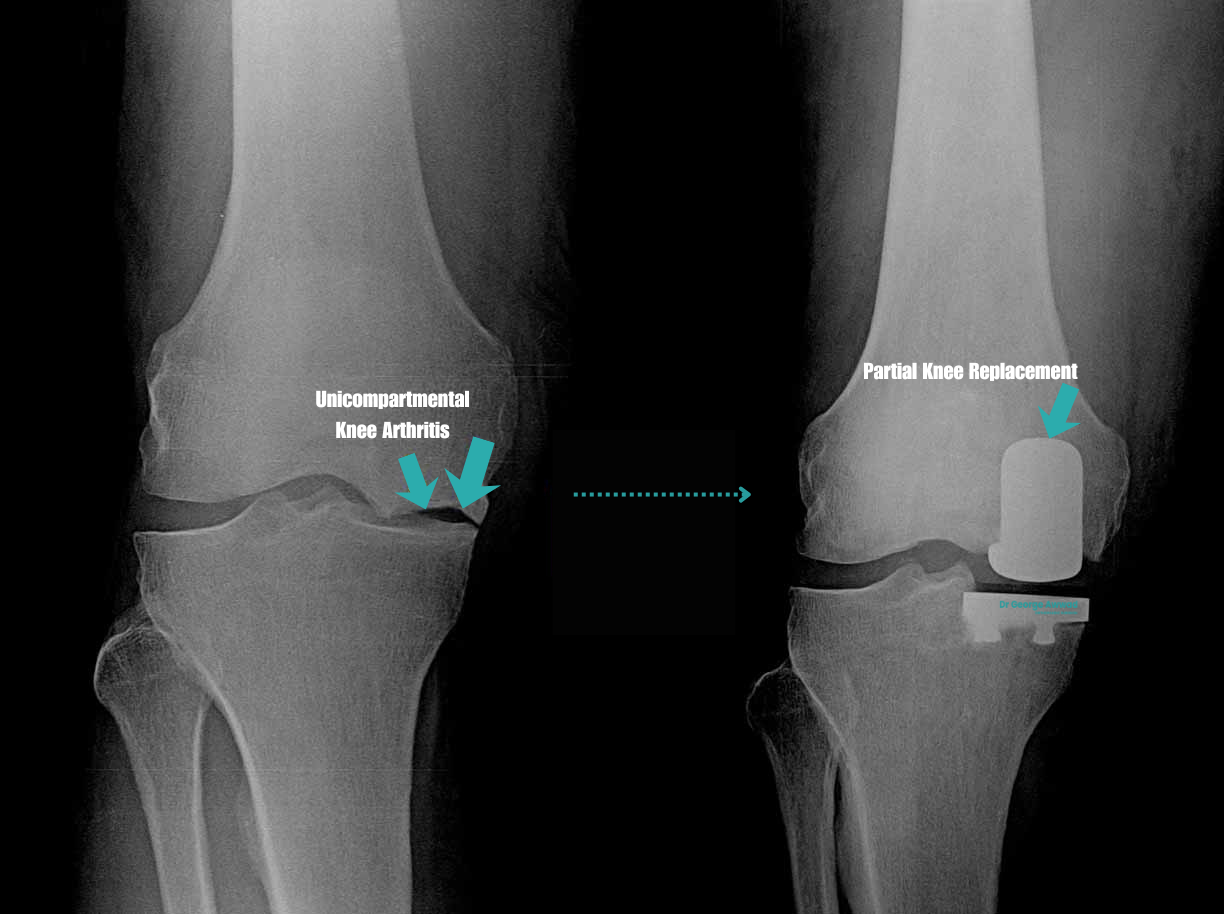

Partial knee replacement (PKR)

Partial knee replacement is a more limited procedure in which only the damaged compartment of the knee is resurfaced. The rest of the knee, including healthy cartilage, ligaments, and the other compartments is preserved.

This procedure may be suitable for patients with:

- Isolated medial or lateral compartment arthritis

- Intact anterior cruciate ligament (ACL)

- Well-preserved range of motion and knee alignment

Because only a portion of the joint is replaced, recovery is often quicker, and the knee may feel more “natural” after surgery.

Potential advantages of PKR:

- Smaller incision and less tissue disruption

- Faster recovery and rehabilitation

- Preservation of more natural knee mechanics

Not all patients however are suitable for this procedure. Dr Awwad will conduct a thorough clinical and imaging assessment to determine if you are a candidate.